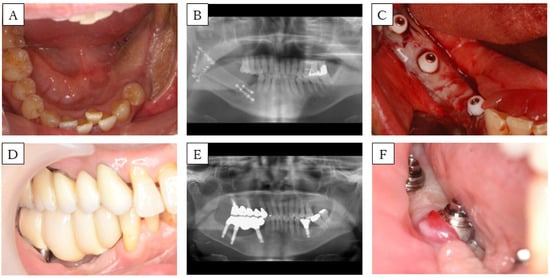

3.1. Case 2 (Method 1)

| Case | Age (years) | Sex | Cause | Mandible Defect Size (cm) | Mucosal Defect Size (cm) | No. of Implants | View | FGG | Fixing Method of Mucosal Graft | Prosthesis | Timing * (months) | Implant Lost |

|---|---|---|---|---|---|---|---|---|---|---|---|---|

| 1 | 46 | M | SCC | 6.5 | 3 × 2 | 2 | ![]() | no | - | Fixed | - | 1 |

| 2 | 58 | F | SCC | 5 | 4.5 × 1.5 | 3 | ![]() | yes ** | Method 1 | Fixed | 0 | 0 |

| 3 | 30 | F | OS | 7 | 5 × 1 | 4 | ![]() | yes | Method 2 | Fixed | 3 | 0 |

| 4 | 63 | M | SCC | 5 | 5 × 4 | 4 | ![]() | yes | (1) Method 2 *** (2) Method 3 | Removable | (1) 7 (2) 31 | 0 |

| 5 | 66 | M | ORN | 17 | All Gingiva | 4 | ![]() | yes | Method 3 | Removable | 0 | 0 |